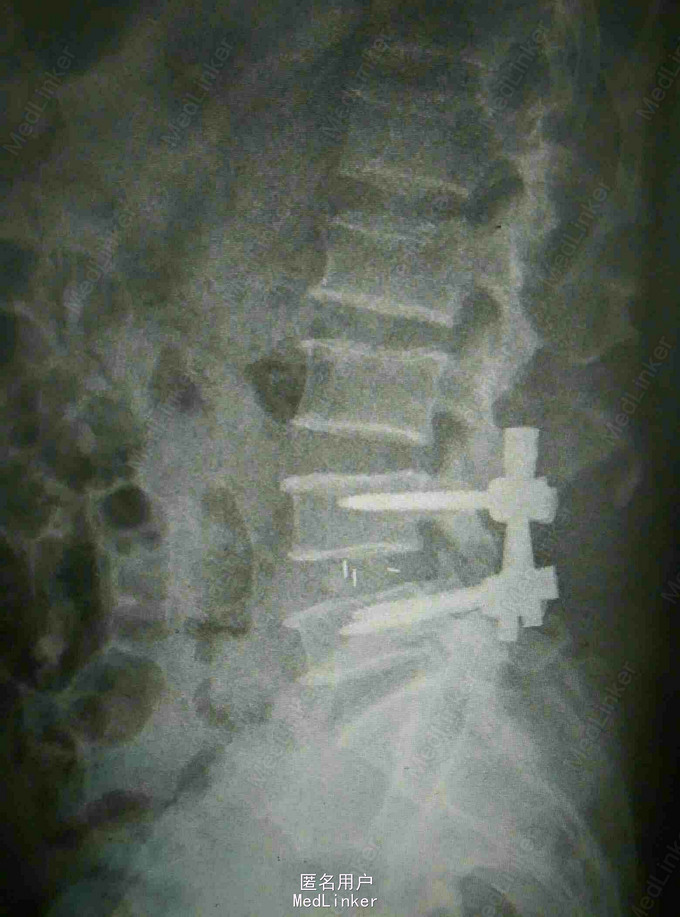

诊断:腰椎间盘突出 马尾神经受压 双下肢不全瘫 治疗:腰椎后路减压植骨融合内固定术

随访:嘱三周后可佩戴腰围下地活动,卧床加强腰背肌肉锻炼,定期复查。 讨论:患者腰椎间盘突出症反复四年,未予重视,无特殊处理,遂进展为大小便障碍,双下肢不全瘫,此时即使手术效果也很差,神经功能恢复困难,典型小病拖大,错失时机。因此对出现下肢症状的患者建议早期手术,一旦进展出现大小便障碍则错失机会。